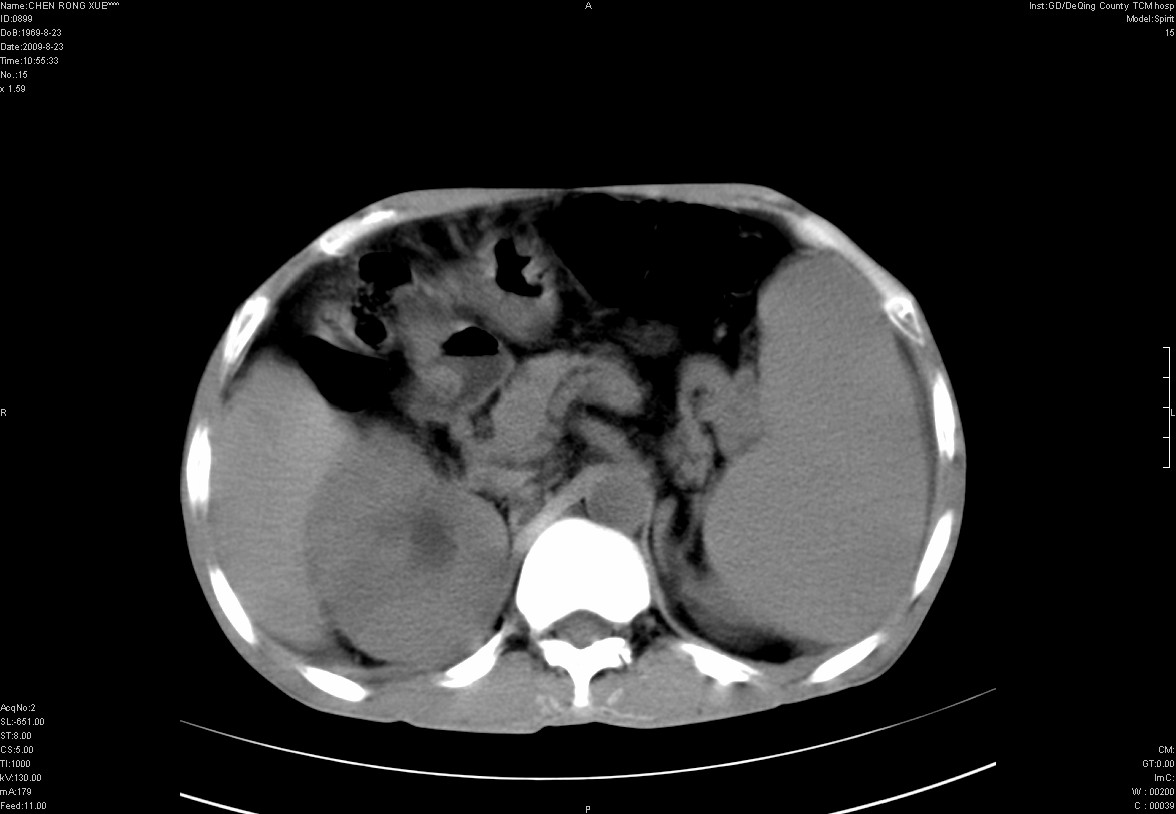

以下是引用zxl51642在2009-8-23 12:56:00的发言:[br]1、肝硬化、脾大;2、慢性胆囊炎;3、右肾占位并右侧腰大肌受侵,考虑恶性可能性大,建议增强扫描进一步检查。

以下是引用qiuleiyu在2009-8-23 15:17:00的发言:[br]1、慢性肝病,肝硬化,脾大,门脉高压。胆囊小结石。[br]2、右肾明显肿大,伴片状低密度灶,累及右侧腰大肌,肿瘤及炎症性病变皆有可能大,建议增强。

以下是引用zjzjr在2009-8-23 17:42:00的发言:[br]1、慢性肝病,肝硬化,脾大,门脉高压。胆囊小结石。[br]右肾脓肿波及肾周,建议增强

以下是引用dyqct在2009-8-23 16:53:00的发言:[br][quote]以下是引用qiuleiyu在2009-8-23 15:17:00的发言:[br]1、慢性肝病,肝硬化,脾大,门脉高压。胆囊小结石。[br]2、右肾明显肿大,伴片状低密度灶,累及右侧腰大肌,炎症性病变可能,建议增强。